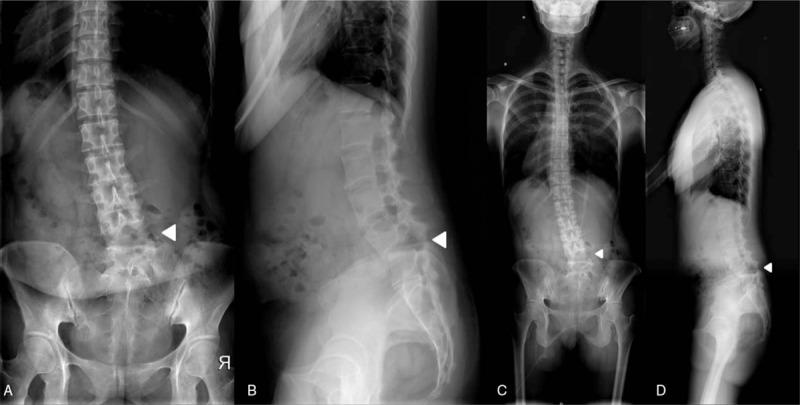

Initial imaging studies revealed a fracture of the left L5 superior articular process with a posterior ligament complex (PLC) injury. Subsequent radiographs showed the locked facet dislocation with kyphotic changes.

The patient underwent surgical reduction and fusion, and the operative findings revealed the L4-5 bilateral facet dislocation and rupture of the PLC at the index level.

初始影像学检查显示L5左侧上关节突骨折伴后韧带复合体(PLC)损伤。随后的X线片显示小关节脱位并伴有脊柱后凸改变。

患者接受了手术复位和融合,术中发现为L4-5双侧小关节脱位及相应节段PLC破裂。